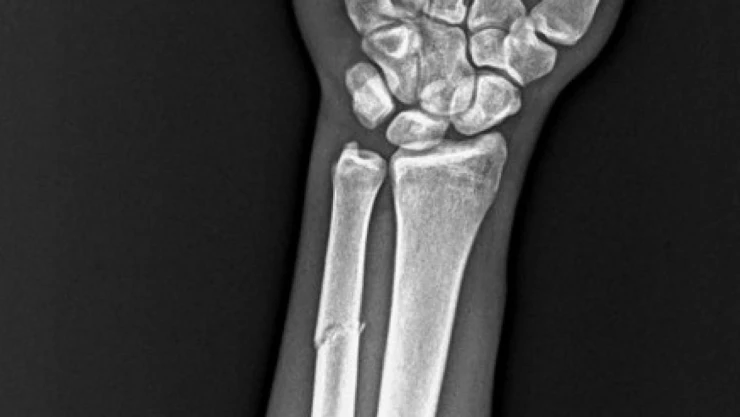

RAMS Başakşehir ile oynanan karşılaşmada mücadele sırasında sakatlanarak oyundan alınan Onuachu’nun sağlık durumu ile ilgili kulübü Trabzonspor bir açıklama yaptı. Yapılan açıklamada, "Futbol A takımımızın Başakşehir ile oynadığı karşılaşma esnasında sakatlanarak oyundan çıkan futbolcumuz Paul Onuachu’nun yapılan muayenesinde sol kasık bölgesinde kas (adduktor kas grubu) yaralanması ve sol ön kolda darbeye bağlı ayrışmamış kemik (ulna) kırığı tespit edilmiştir. Oyuncumuzun tedavisine sağlık ekibimizce başlanmıştır. Oyuncunun sahalardan ne kadar süre uzak kalacağı yapılacak tedavinin ardından belli olacak" ifadelerine yer verildi.